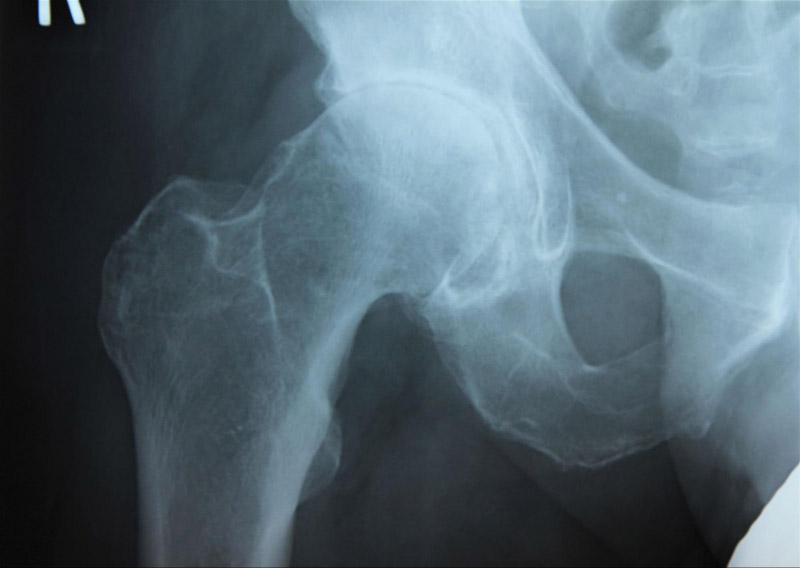

Cấp độ 3 – Trung bình: Khe khớp hẹp nhiều, xuất hiện gai nhỏ cùng hiện tượng cứng xương dưới sụn, kèm theo biến dạng nhẹ ở đầu xương đùi và ổ cối.

Hình chụp X-quang xương chậu cho thấy biến dạng nhẹ tại đầu xương đùi ở bên hông phải.Hình ảnh X-quang khớp biến dạng ở một bên hông.